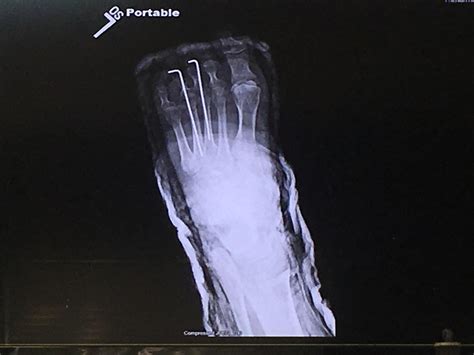

This is my foot after a long trip. : r/FootFetish